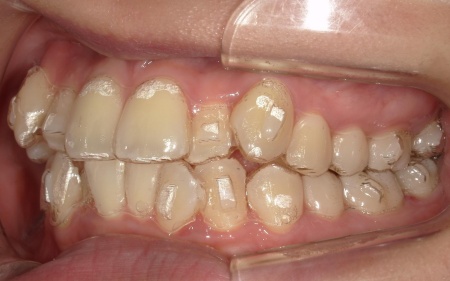

20代女性 八重歯と歯並びの乱れをマウスピース矯正装置で改善した症例

拝見したところ、歯が正しく並ぶためのスペースが不足しており、歯が重なって生えてしまう叢生(そうせい)の状態が全体的に見られました。

特に上下の糸切り歯が外側にずれている、いわゆる八重歯が目立っています。

歯並びを改善する方法として、透明なマウスピースを段階的に交換しながら歯を動かしていくインビザラインコンプリヘンシブパッケージによる矯正治療を提案し、同意いただきました。

今回は②のIPRで対応できる範囲と判断し、メリット・デメリットを説明したうえで治療を開始しました。

治療と並行して、歯と歯の間にスペースを作るためのIPRを適切なタイミングで実施しました。また、噛む力が強い傾向が見られたため、奥歯の噛み込みを抑え、歯をスムーズに動かすために「バイトランプ」と呼ばれる小さな突起をマウスピースの上の前歯の裏側に設置しています。